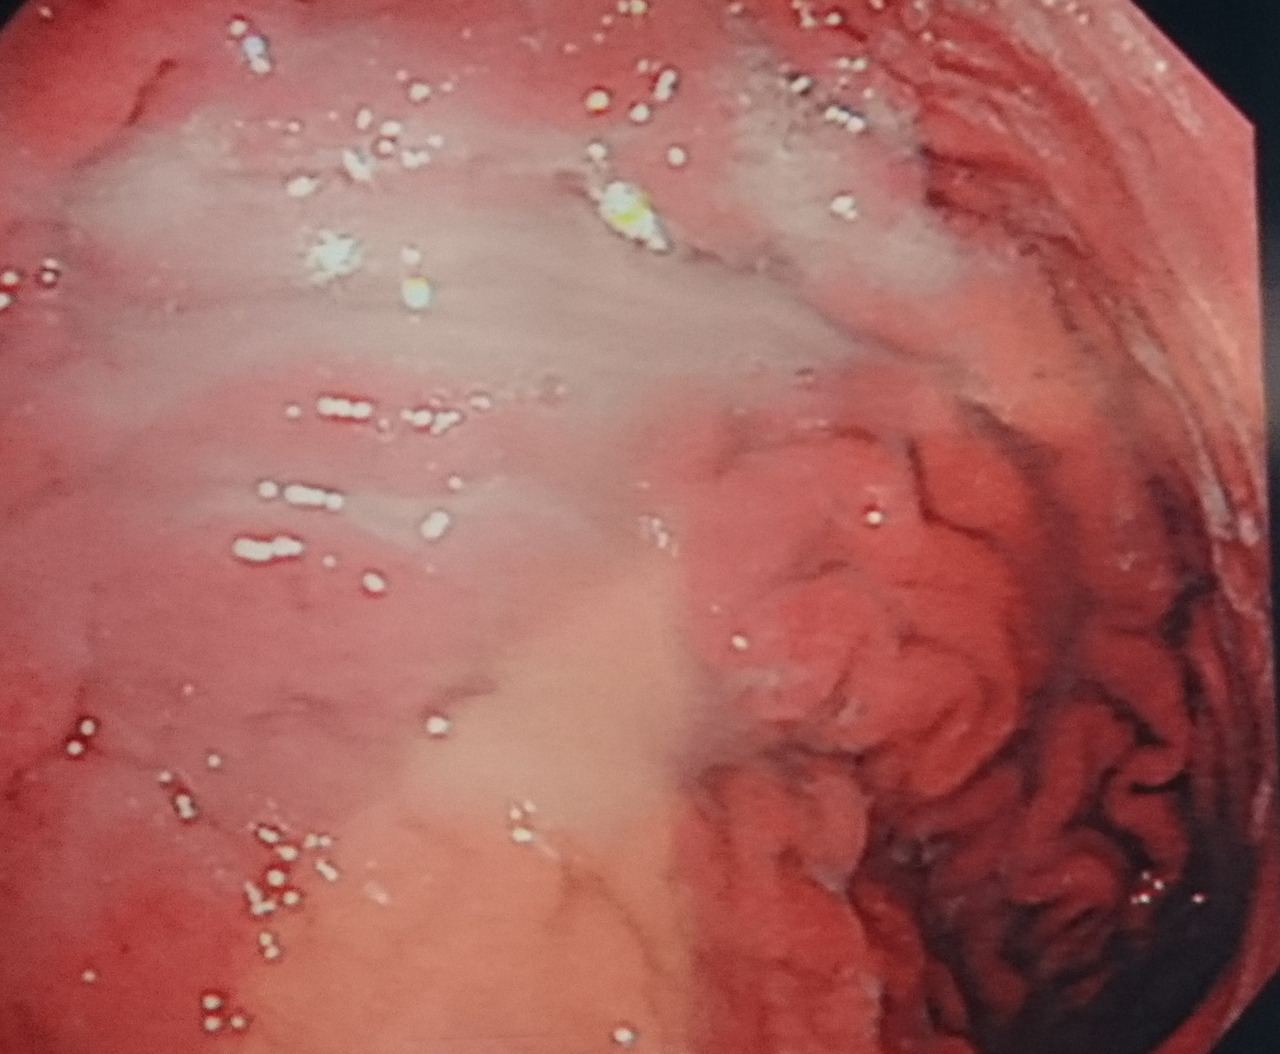

위축성 위염 및 장상피화생 평가

- 위점막의 얇아짐, 창백함

- 위산 분비 감소

- 장점막 형태가 나타나는 변화

이 두 가지 변화는 위암의 전구 병변으로 간주되기 때문에 정기적인 조직검사 추적이 중요합니다.